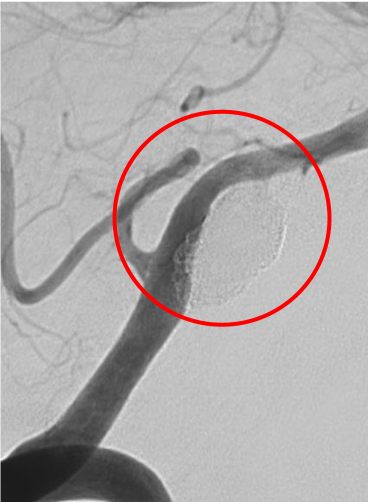

術前の造影写真です。〇内に脳動脈瘤が造影されています。

術直後の造影写真ではまだ脳動脈瘤は造影されています。

半年後の造影写真では脳動脈瘤は完全に消失しています。